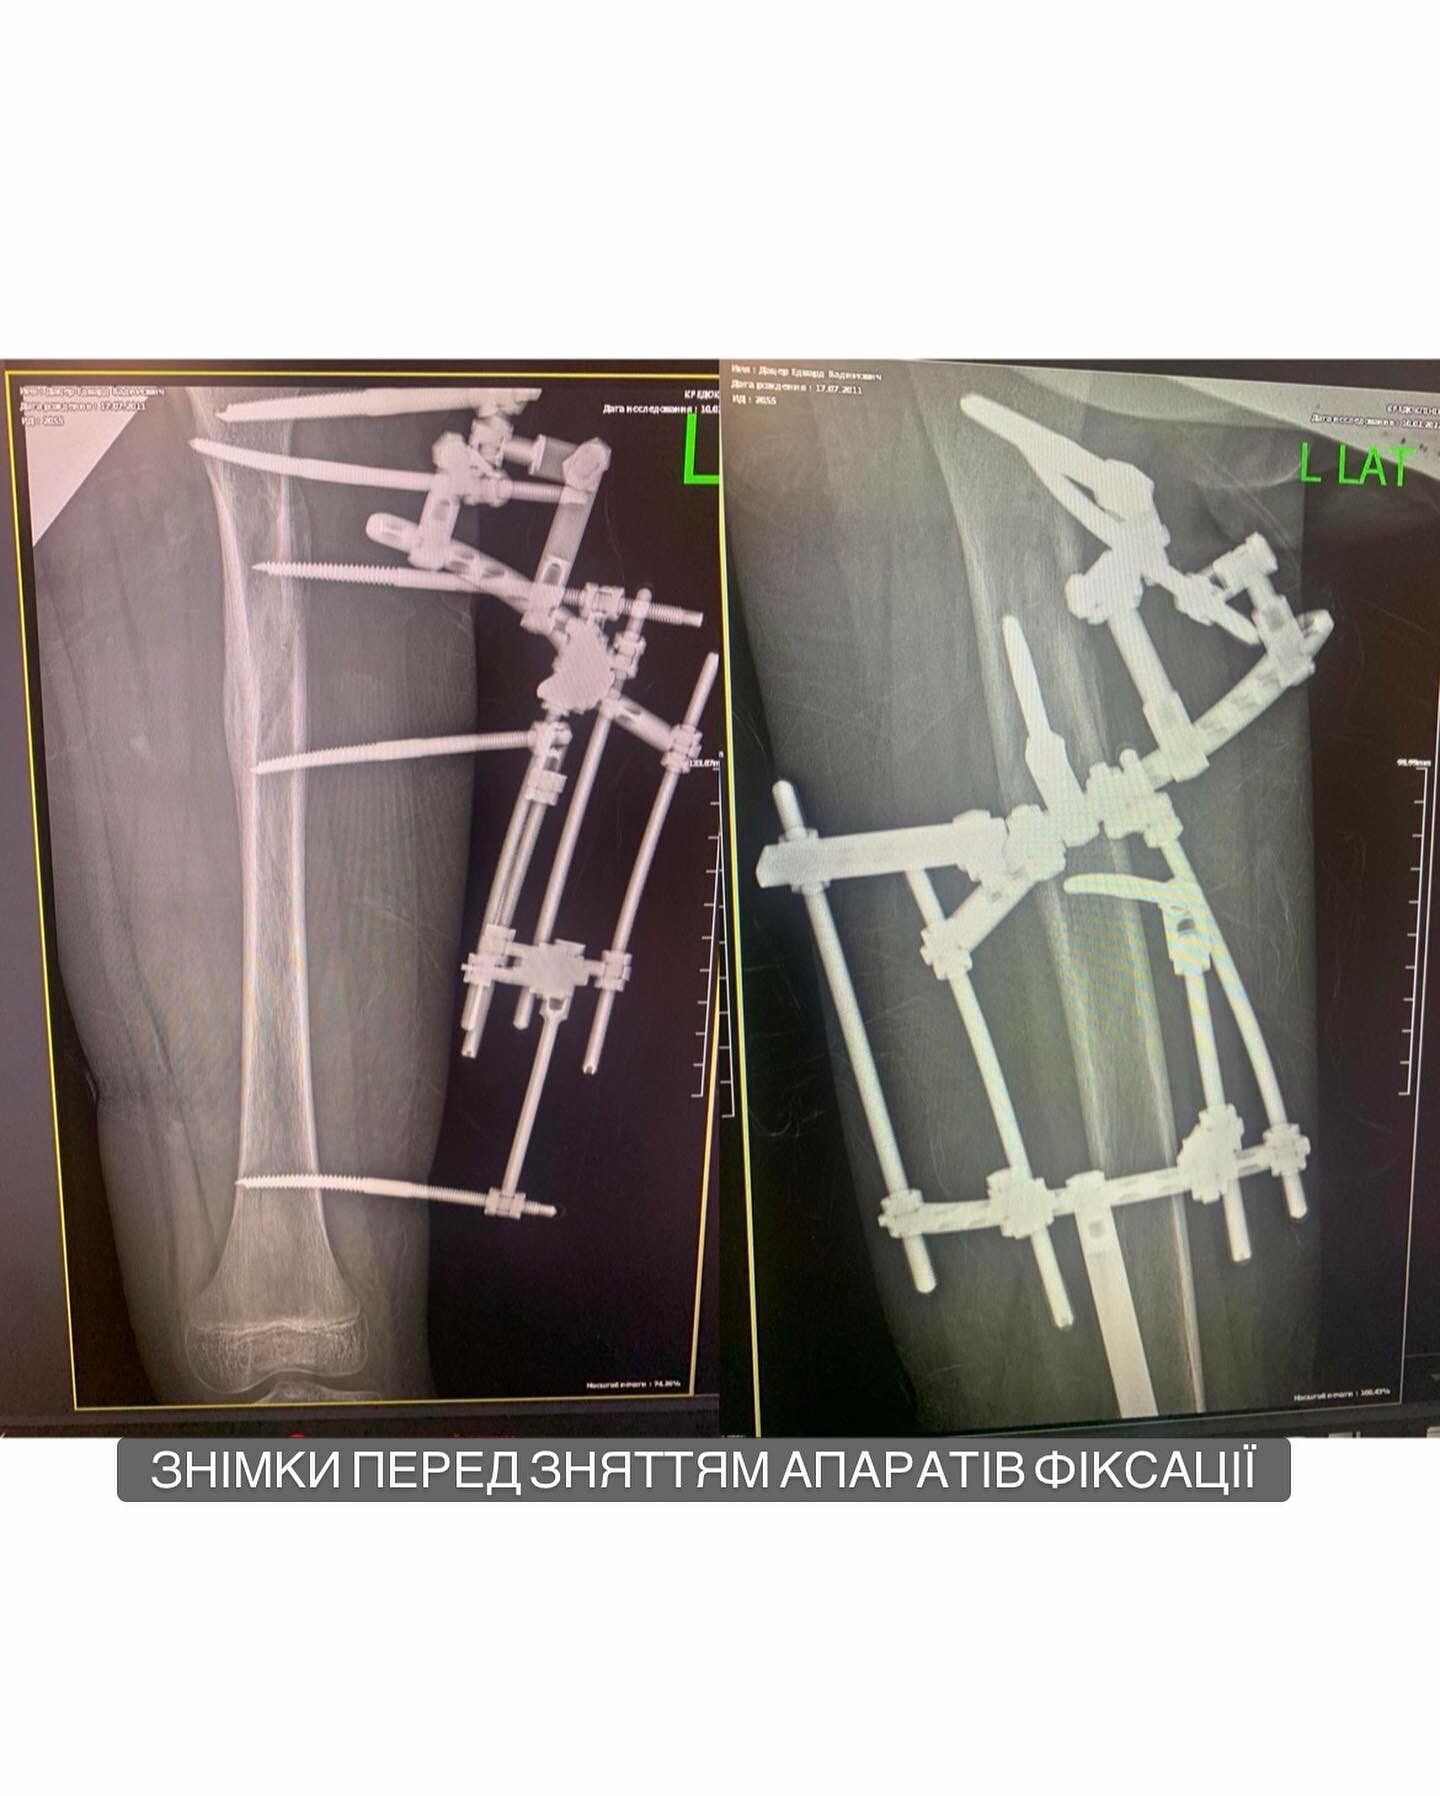

⚡️Діагноз: закритий перелом лівої бедренной кістки з розміщенням обломків в середньому третьому бедрі. Врач: Веклич В.В.

1-2 фото перед снятием;